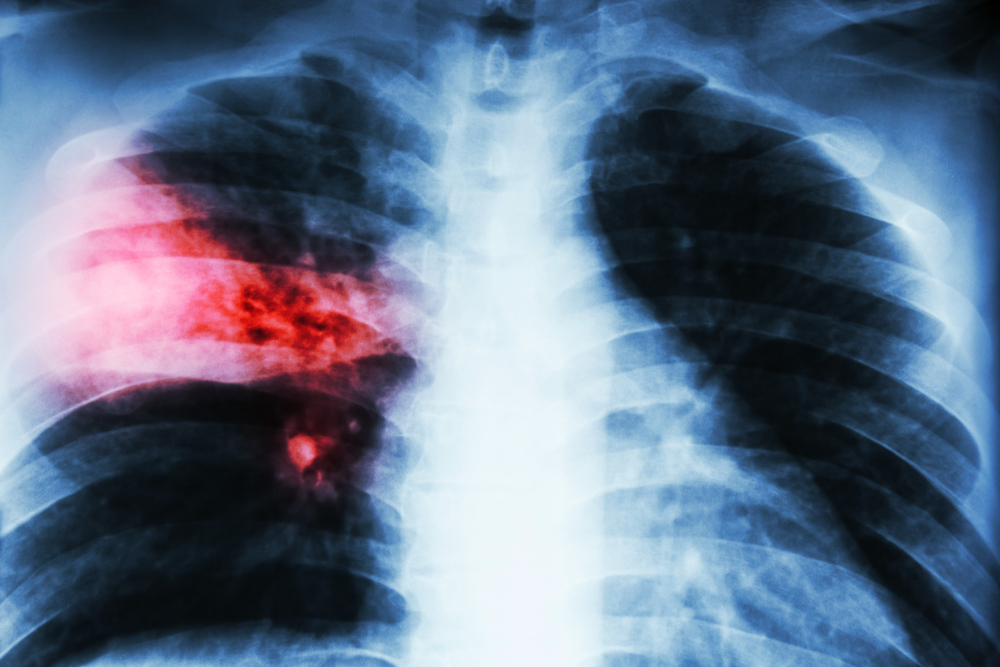

Doctors will diagnose lobar pneumonia by looking at your symptoms and your health history. Typically, blood tests or sputum cultures will be done to look for bacteria. Doctors may do other tests, including X-rays and CT scans, to rule out other categories of pneumonia and other diseases. Often, though, a simple physical examination and a look at your health records are enough to determine if you likely have pneumonia or not. Tests are usually only done to determine the category of pneumonia in order to correctly treat it.